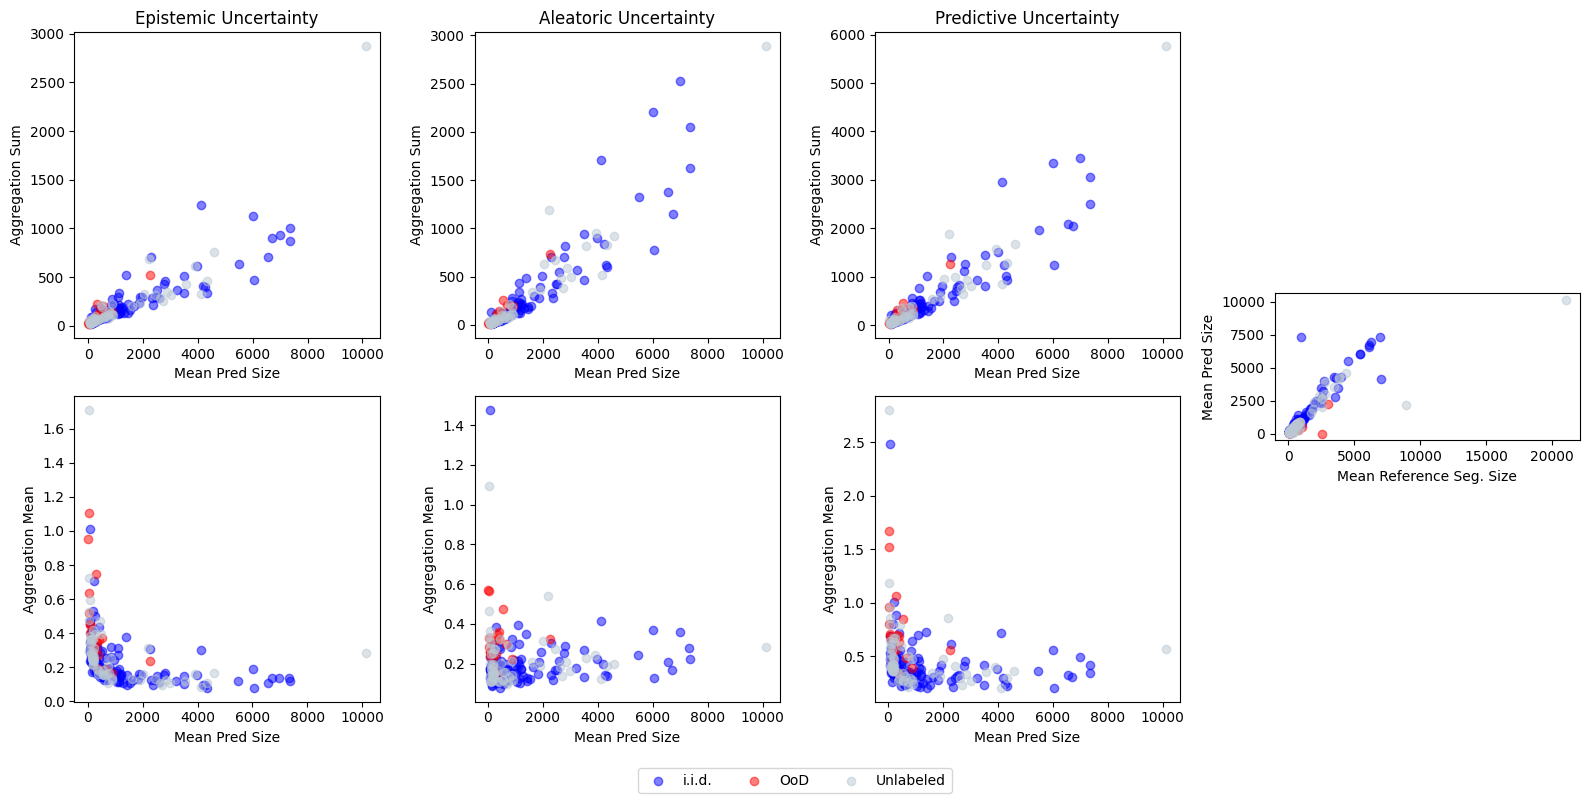

C3: Aggregation Strategy We validate three different aggregation strategies, taking the pixel-level uncertainties as input and returning one score per image: 1) Image level aggregation, as used in Czolbe et al. (2021); Gonzalez et al. (2021); Jungo et al. (2020), where uncertainty scores for all pixels are summed per image. We find that for segmentation maps with one single object in the foreground, the uncertainty score directly correlates with the size of the target object (see Appendix F). Thus, we only use this aggregation strategy on the GTA5/CS dataset. 2) Patch level aggregation, which uses a sliding window of size ( is the dimensionality of the image) to sum the uncertainties inside the window, and then selects the patch with the highest uncertainty as the image-level uncertainty score. 3) Threshold level aggregation considers only uncertainty scores above a threshold (see Appendix F for how this threshold is determined) as uncertain, and calculates the mean of those scores. Notably, as selecting the threshold depends on the foreground object size, this strategy is not applicable to the GTA5/CS dataset.

F.1 Ablation study: Correlation of image level aggregation and object size

To confirm the hypothesis about the correlation between the object size and the amount of uncertainty, we generated plots to see the connection between those two variables for the LIDC datasets. One of the generated plots is shown in Figure 8. This plot is for a TTD model on the LIDC TEX dataset. In the top row, the aggregated amount of uncertainty compared to the mean size of the predicted segmentation is shown for the epistemic, the aleatoric, and the predictive uncertainty. In the bottom row, the summed uncertainty is divided by the object size. To confirm that the size of the predicted segmentation corresponds to the ground truth segmentation size, the two variables are plotted on the right-hand side. It can be seen, that a positive correlation between the aggregation sum and the object size is given in the top row, but if the aggregation mean is taken in the bottom row, this correlation is not present. This means that the summed uncertainty only correlates with the size of the objects and does not represent the objects’ uncertainty independent of the size.